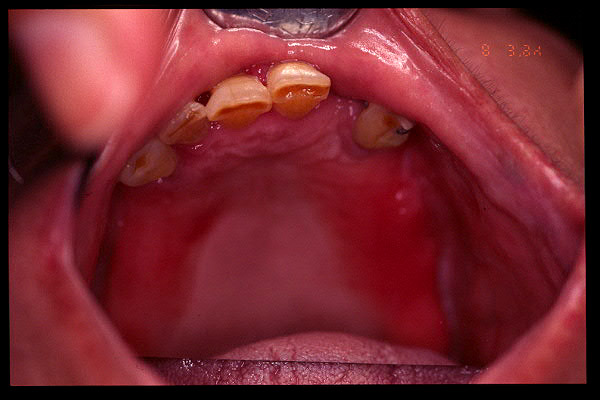

CM Extrusión de incisivos inferiores por falta de contactos oclusales